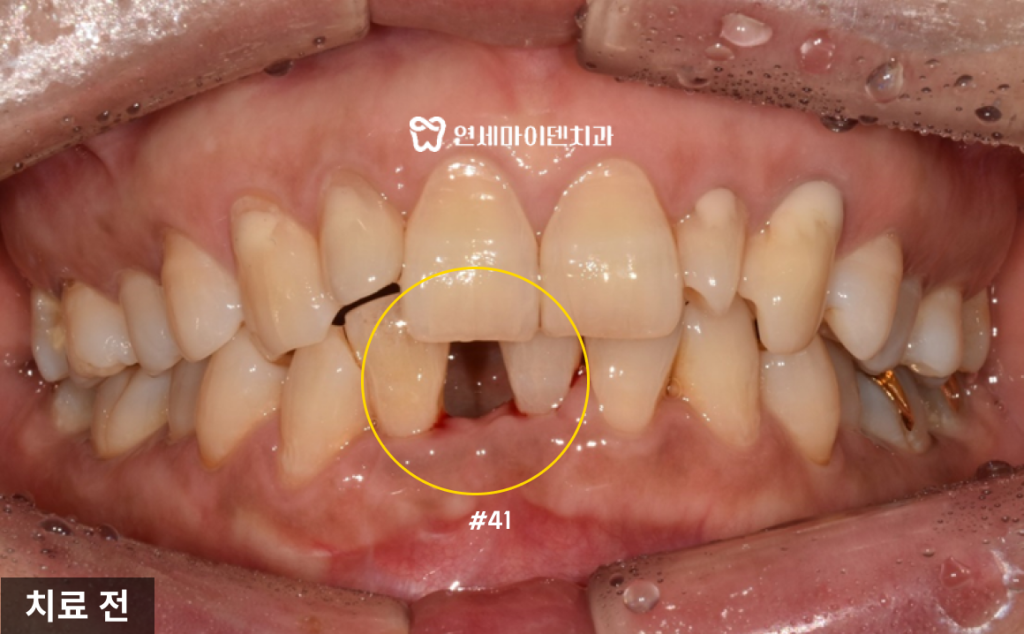

치료 전 환자분의 상태를 확인했는데,

앞니를 발치한 자리는 공간이 상당히 좁았습니다.무엇보다도 가장 큰 문제는

3개월 동안 임시치아 없이 지낸 점이었습니다.

발치 이후에는 임시치아를 가능한 빨리 장착해야

치조골이 내려앉지 않고 공간도 유지됩니다.하지만, 발치 후 빈 공간을 그대로 놔두게 되면

잇몸 뼈가 흡수되고 잇몸 형태도 무너지게 됩니다.실제로 이 환자분의 경우

발치 부위의 잇몸 뼈가 아직 회복되지 않은 채

엑스레이 상으로 까맣게 흡수되어있는게 보입니다.양옆 치아 뿌리에도 영향을 줄 수 있는 상태였습니다.